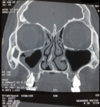

DESCRIBE ESTA TAC Y DX

* imagen de ocupación parcial en el seno maxilar derecho de un 30% de ocupación, periférico, marginal * otra imagen de ocupación periférica, marginal * desviación septal hacia la derecha posiblemente de características óseas (porque se ve blanco) * se observa una hipertrofia del cornete inferior izq, superficie irregular (degeneración polipoidea = en un futuro puede desarrollar pólipos) * etmoidales = ocupación **dx = sinusitis maxiloetmoidal bilateral, desviación septal e hipertrofia del cornete inferior izq con degeneración polipoidea (sobre la base de esta imagen!!!)** * definir si hay imagen de ocupación (posible sinusitis, le ponemos apellido), bilateral o unilateral, qué seno (cuál o son varios) y todo lo demás patológico qué vean